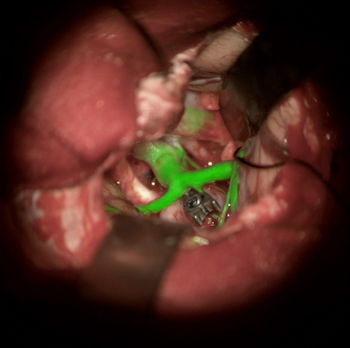

Leica Microsystems says the tech enables surgeons to make critical decisions when they matter most.